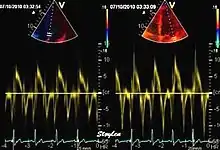

Tissue Doppler echocardiography (TDE) is a medical ultrasound technology, specifically a form of echocardiography that measures the velocity of the heart muscle (myocardium) through the phases of one or more heartbeats by the Doppler effect (frequency shift) of the reflected ultrasound. The technique is the same as for flow Doppler echocardiography measuring flow velocities. Tissue signals, however, have higher amplitude and lower velocities, and the signals are extracted by using different filter and gain settings. The terms tissue Doppler imaging (TDI) and tissue velocity imaging (TVI) are usually synonymous with TDE because echocardiography is the main use of tissue Doppler.

Like Doppler flow, tissue Doppler can be acquired both by spectral analysis (spectral density estimation) as pulsed Doppler[1] and by the autocorrelation technique as colour tissue Doppler[2] (duplex ultrasonography). While pulsed Doppler only acquires the velocity at one point at a time, colour Doppler can acquire simultaneous pixel velocity values across the whole imaging field. Pulsed Doppler on the other hand, is more robust against noise, as peak values are measured on top of the spectrum, and are unaffected of the presence of clutter (stationary reverberation noise).